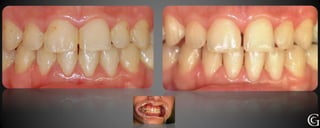

Evidencias clinicas